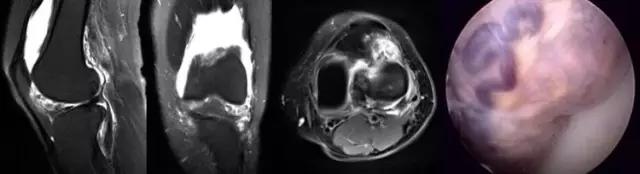

我们可能都不熟悉T1、T2,怎么办?当我们发现有问题后,利用照片上图像的对比,推测病变的可能也是一种诊断方法。病例:黄XX,女,39岁,左膝关节反复交锁1年。图1:肿物信号与骨信号一样图2:肿物信号与骨信号一样图3:肿物信号与骨信号不一样 肿物应该与骨相关,但不是骨性,推断:膝关节滑膜软骨瘤。手术后得到证实。